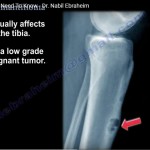

Adamantinoma

Courtesy:Prof Nabil Ebraheim, University of Toledo, Ohio, USA